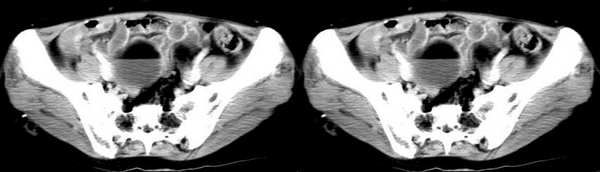

女,55岁,因下腹胀痛2月,b超发现盆腔包块7天,而入院,检查:右侧附件如女拳头大小包块,活动差,轻压痛,质中,子宫稍正常缩小,彩超示子宫4.9cmx2.6cmx2.3cm ,右侧附件包块示:8.7cmx9.1cmx6.3cm 的混合性回声,脂质分层征

双侧卵巢畸胎瘤,右侧为著

畸胎瘤(两侧)

双侧卵巢畸胎瘤

畸胎瘤,可见典型脂肪-液体征象。

畸胎瘤,脂-液分层